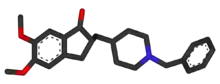

Curcumin as of 2010 had not shown benefit in people even though there is tentative evidence in animals.[169] There was inconsistent and unconvincing evidence that ginkgo has any positive effect on cognitive impairment and dementia.[170] As of 2008 there was no concrete evidence that cannabinoids are effective in improving the symptoms of AD or dementia;[171] however, some research into endocannabinoids looked promising.[172]

Five medications are currently used to treat the cognitive problems of AD: four are acetylcholinesterase inhibitors (tacrine, rivastigmine, galantamine and donepezil) and the other (memantine) is an NMDA receptor antagonist. The benefit from their use is small.[173][174][175] No medication has been clearly shown to delay or halt the progression of the disease.

Reduction in the activity of the cholinergic neurons is a well-known feature of Alzheimer's disease.[176] Acetylcholinesterase inhibitors are employed to reduce the rate at which acetylcholine (ACh) is broken down, thereby increasing the concentration of ACh in the brain and combating the loss of ACh caused by the death of cholinergic neurons.[177] There is evidence for the efficacy of these medications in mild to moderate Alzheimer's disease,[178][174][173] and some evidence for their use in the advanced stage.[173] The use of these drugs in mild cognitive impairment has not shown any effect in a delay of the onset of AD.[179] The most common side effects are nausea and vomiting, both of which are linked to cholinergic excess. These side effects arise in approximately 10–20% of users, are mild to moderate in severity, and can be managed by slowly adjusting medication doses.[180] Less common secondary effects include muscle cramps, decreased heart rate (bradycardia), decreased appetite and weight, and increased gastric acid production.[178]

Glutamate is an excitatory neurotransmitter of the nervous system, although excessive amounts in the brain can lead to cell death through a process called excitotoxicity which consists of the overstimulation of glutamate receptors. Excitotoxicity occurs not only in Alzheimer's disease, but also in other neurological diseases such as Parkinson's disease and multiple sclerosis.[181] Memantine is a noncompetitive NMDA receptor antagonist first used as an anti-influenza agent. It acts on the glutamatergic system by blocking NMDA receptors and inhibiting their overstimulation by glutamate.[181][182] Memantine has been shown to have a small benefit in the treatment of moderate to severe Alzheimer's disease.[183] Reported adverse events with memantine are infrequent and mild, including hallucinations, confusion, dizziness, headache and fatigue.[184] The combination of memantine and donepezil has been shown to be "of statistically significant but clinically marginal effectiveness".[185]

One area of clinical research is focused on treating the underlying disease pathology. Reduction of beta-amyloid levels is a common target of compounds[257] (such as apomorphine) under investigation. Immunotherapy or vaccination for the amyloid protein is one treatment modality under study.[258] Unlike preventive vaccination, the putative therapy would be used to treat people already diagnosed. It is based upon the concept of training the immune system to recognise, attack, and reverse deposition of amyloid, thereby altering the course of the disease.[259] An example of such a vaccine under investigation was ACC-001,[260][261] although the trials were suspended in 2008.[262] Another similar agent is bapineuzumab, an antibody designed as identical to the naturally induced anti-amyloid antibody.[263] However, immunotherapeutic agents have been found to cause some concerning adverse drug reactions, such as amyloid-related imaging abnormalities.[264] Other approaches are neuroprotective agents, such as AL-108,[265] and metal-protein interaction attenuation agents, such as PBT2.[266] A TNFα receptor-blocking fusion protein, etanercept has showed encouraging results.[267]

In 2008, two separate clinical trials showed positive results in modifying the course of disease in mild to moderate AD with methylthioninium chloride, a drug that inhibits tau aggregation,[268][269] and dimebon, an antihistamine.[270] The consecutive phase-III trial of dimebon failed to show positive effects in the primary and secondary endpoints.[271][272][273] Work with methylthioninium chloride showed that bioavailability of methylthioninium from the gut was affected by feeding and by stomach acidity, leading to unexpectedly variable dosing.[274] A new stabilised formulation, as the prodrug LMTX, is in phase-III trials (in 2014).[275]